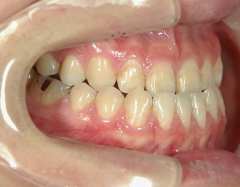

矯正歯科 治療後矯正歯科 全顎ワイヤー矯正 治療後矯正歯科(全顎ワイヤー矯正)治療後

主訴:受け口(反対咬合)を治したい

矯正歯科 治療前 急速拡大装置で上顎を広げた後、ワイヤーへ移行 非抜歯

no.31_7964_治療後_右 .JPGno.31_7964_治療後_正面 .JPGno.31_7964_治療後_左.JPG